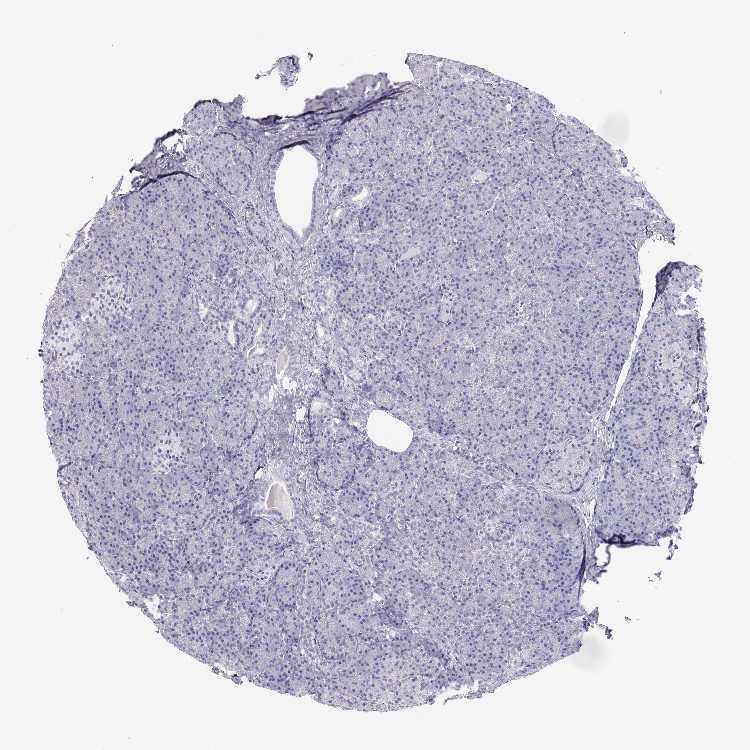

TISSUE PRIMARY DATA PANCREAS Show tissue menu

PANCREAS - Antibody stainingi

Antibody staining in the annotated cell types in the current human tissue is reported as not detected, low, medium, or high, based on conventional immunohistochemistry profiling in selected tissues. This score is based on the combination of the staining intensity and fraction of stained cells.

Each image is clickable and will lead to virtual microscopy that enables deeper exploration of all samples and also displays staining intensity scores, fraction scores and subcellular localization as well as patient and tissue information for each sample.

Antibody HPA038285Antibody HPA058310

Exocrine glandular cells Not detectedNot detected

Pancreatic endocrine cells Not detectedNot detected